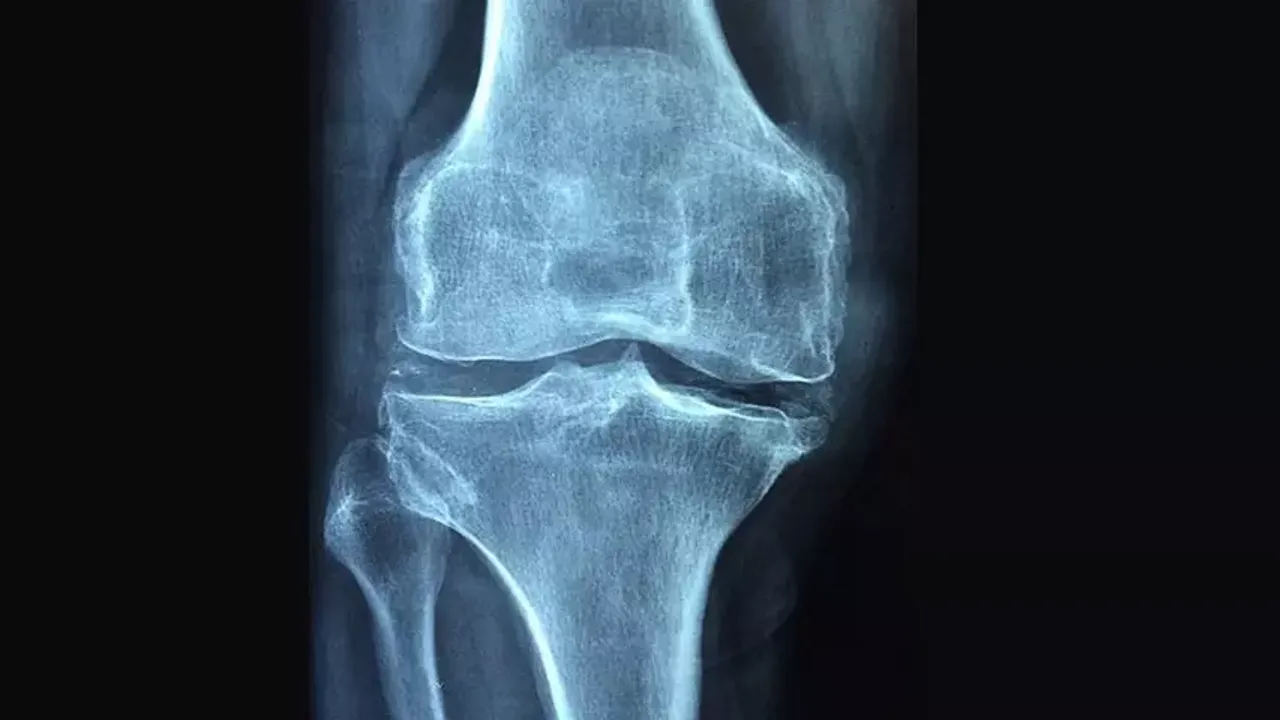

HALK arasında "kemik erimesi" olarak adlandırılan osteoporozu "kemiklerin zayıflayarak kırılgan hale gelmesi" şeklinde tanımlayan Uzm. Dr. Esra Tutal, hastalığın kemiklerin çok ufak travmalarda bile kolayca kırılmalarına neden olabildiğini söyledi. Konuyla ilgili önemli bilgiler paylaşan Uzm. Dr. Esra Tutal, osteoporozun kırık gelişine kadar hastalarda hiçbir belirti vermeyebileceğini işaret etti.

Kemik erimesine bağlı kırıkların en çok kalça, bel ve bilek kemiklerinde görüldüğünü vurgulayan Uzm. Dr. Esra Tutal, "Osteoporoz hem kadınları hem de erkekleri etkileyen bir hastalıktır. Kemik erimesi çok ileri dönemlere kadar herhangi bir belirti vermez. İleri dönemlerde ise sırt ağrısı, bel ağrısı, boyun zamanla kısalması ve duruş bozukluğu (kamburluk) meydana gelir" dedi.

İnsan vücudunda kemik yapım ve yıkımının belli bir denge içerisinde olduğunun altını çizen Uzm. Dr. Esra Tutal, "20 yaşına kadar kemik yapımı ön plandadır. 30 yaşına kadar maksimum kemik kitlesi oluşur. 30 yaşından sonra ise yıkım ön plana geçer. Maksimum kemik kitlesi ne kadar iyi ise vücut yıkımdan o kadar az etkilenir. Kadınlar, yaşlılar, ailesinde kırık öyküsü olanlar ve zayıf minyon yapılı olanlarda daha sık görülür. Ayrıca romatizma tedavisinde kullanılan kortizonlu ilaçlar, epilepsi ilaçları, kanser ilaçları, bazı mide ilaçları kullanmak, romatiod artrit, kanser, lupus, multipe myleom, böbrek karaciğer hastalıkları gibi hastalıklar geçirmek, hareketsiz bir yaşama sahip olmak, sigara kullanmak, sık alkol kullanmak, besinlerle yeterince kalsiyum almamak, aşırı miktarda tiroit hormonu kullanmak, aşırı zayıf olmak, gereğinden daha az beslenmek ve zayıflama ameliyatı olmak da kemik erimesine neden olabilir. Kemik erimesi omurlarda, el bileğinde ve kalça kemiğinde kırılmalara yol açarak sakatlıklara hatta ölümlere yol açabilir" diye konuştu.